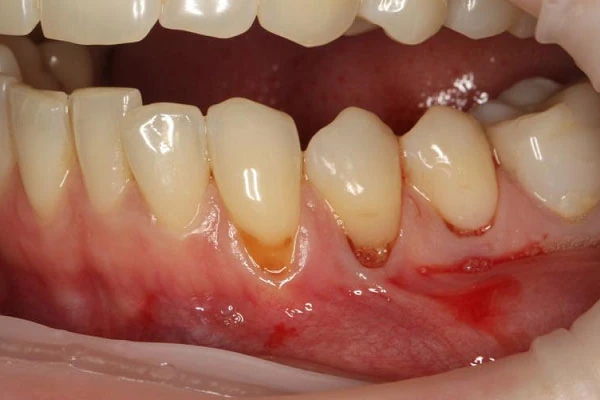

- рецессии (оголение корня зуба)

Хирургическое закрытие рецессии в области 1-го зуба (тоннельный, лоскутный методы)38 000 ₽

Хирургическое закрытие множественных рецессий 1-го сегмента - от 4 до 6 зубов (тоннельный, лоскутный методы)75 900 ₽

Сложное хирургическое закрытие множественных рецессий 1-го сегмента - от 4 до 6 зубов (тоннельный, лоскутный методы)91 000 ₽